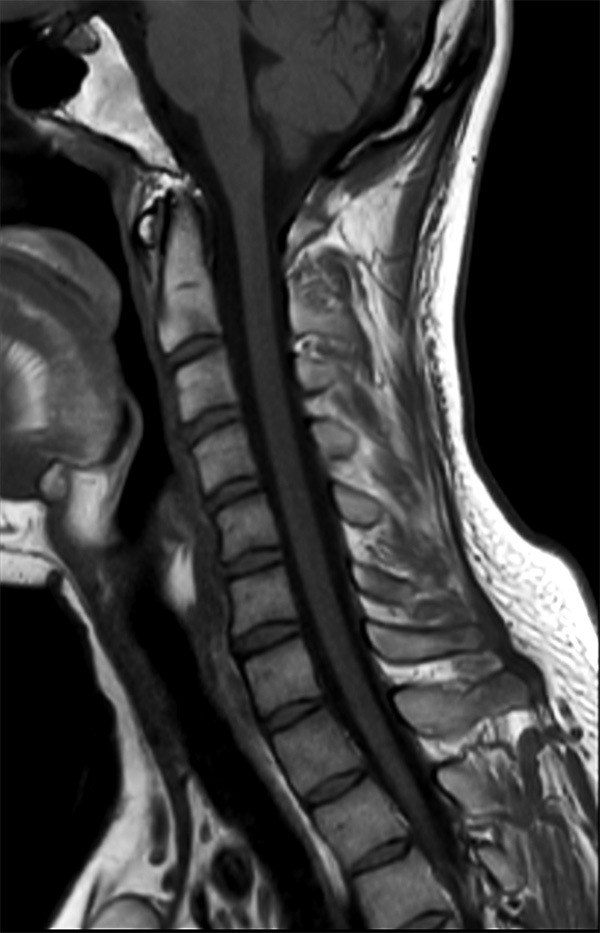

Comprehensive Cervical Spine imaging at 1.5T